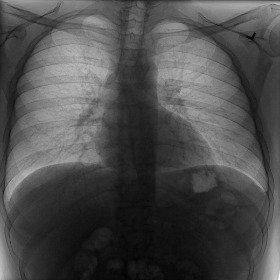

Fig. 3 shows image samples from the above datasets.

Figure 3: Image diversity across four datasets: (a) JSRT, (b) Montgomery County X-ray, (c) NIH ChestX-ray14, and (d) CheXpert